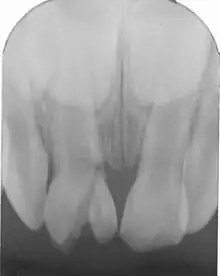

Fracture radiculaire

Fracture radiculaire : fracture de la dentine, du cément et de la pulpe avec ou sans déplacement du fragment coronaire. Dans ce cas une mobilité axiale et/ou latérale de la dent avec une élongation coronaire survient[1], plus ou moins prononcée et une gêne à l'occlusion.